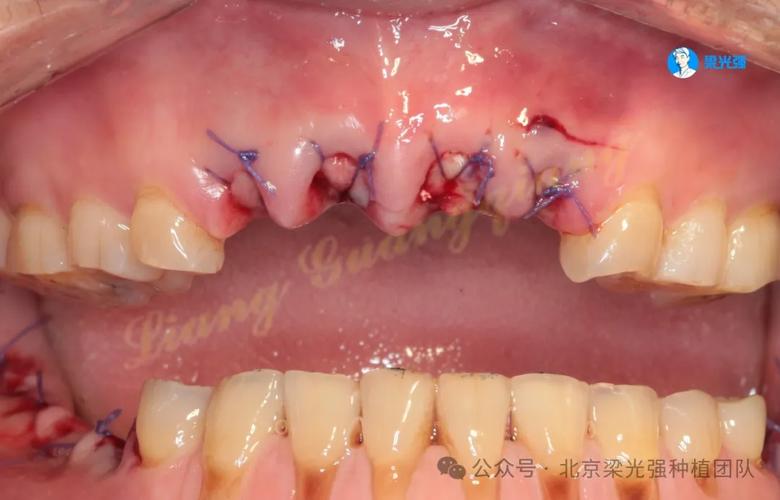

一旦怀疑种牙失败,需立即就医,医生会通过临床检查(如探诊、叩诊、松动度测试)和影像学检查(CBCT、X光片)明确失败原因,常见的处理方式包括:若为感染性失败(如种植体周围炎),需进行翻瓣清创、局部上药,并配合全身抗生素控制炎症;若骨结合失败(种植体与骨组织未融合),则需取出种植体,待炎症消退后评估骨量,必要时进行植骨,等待3-6个月骨愈合后再考虑二次种植;若为机械并发症(如种植体折断、基台松动),需根据折断位置选择取出修复或更换部件。